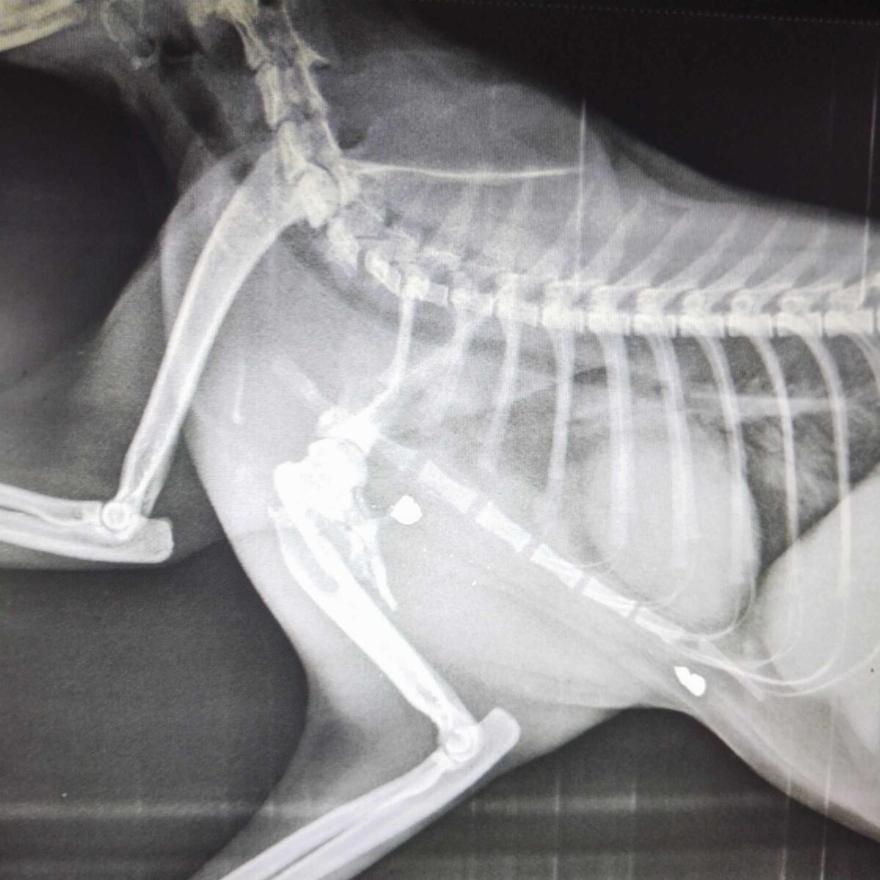

«Αιμορραγούσε. Μεταφέρθηκε την ίδια μέρα στην Αλεξανδρούπολη. Σήμερα τα ευρήματα της ακτινογραφίας αποκάλυψαν μια από τις πιο νοσηρές ιστορίες κακοποίησης. Η Ναόμι ήταν δεύτερη φορά χτυπημένη από όπλο. Βρέθηκαν δύο σφαίρες. Μια παλιά που δικαιολογεί τον τραυματισμό της, το Μάρτιο και μια νέα, η χθεσινή. Αυτή τη φορά το κτήνος που την σημάδεψε της είχε σπάσει το οστό,» περιγράφει.

Έγινε χειρουργική επέμβαση αποκατάστασης και αφαιρέθηκαν και οι δύο σφαίρες